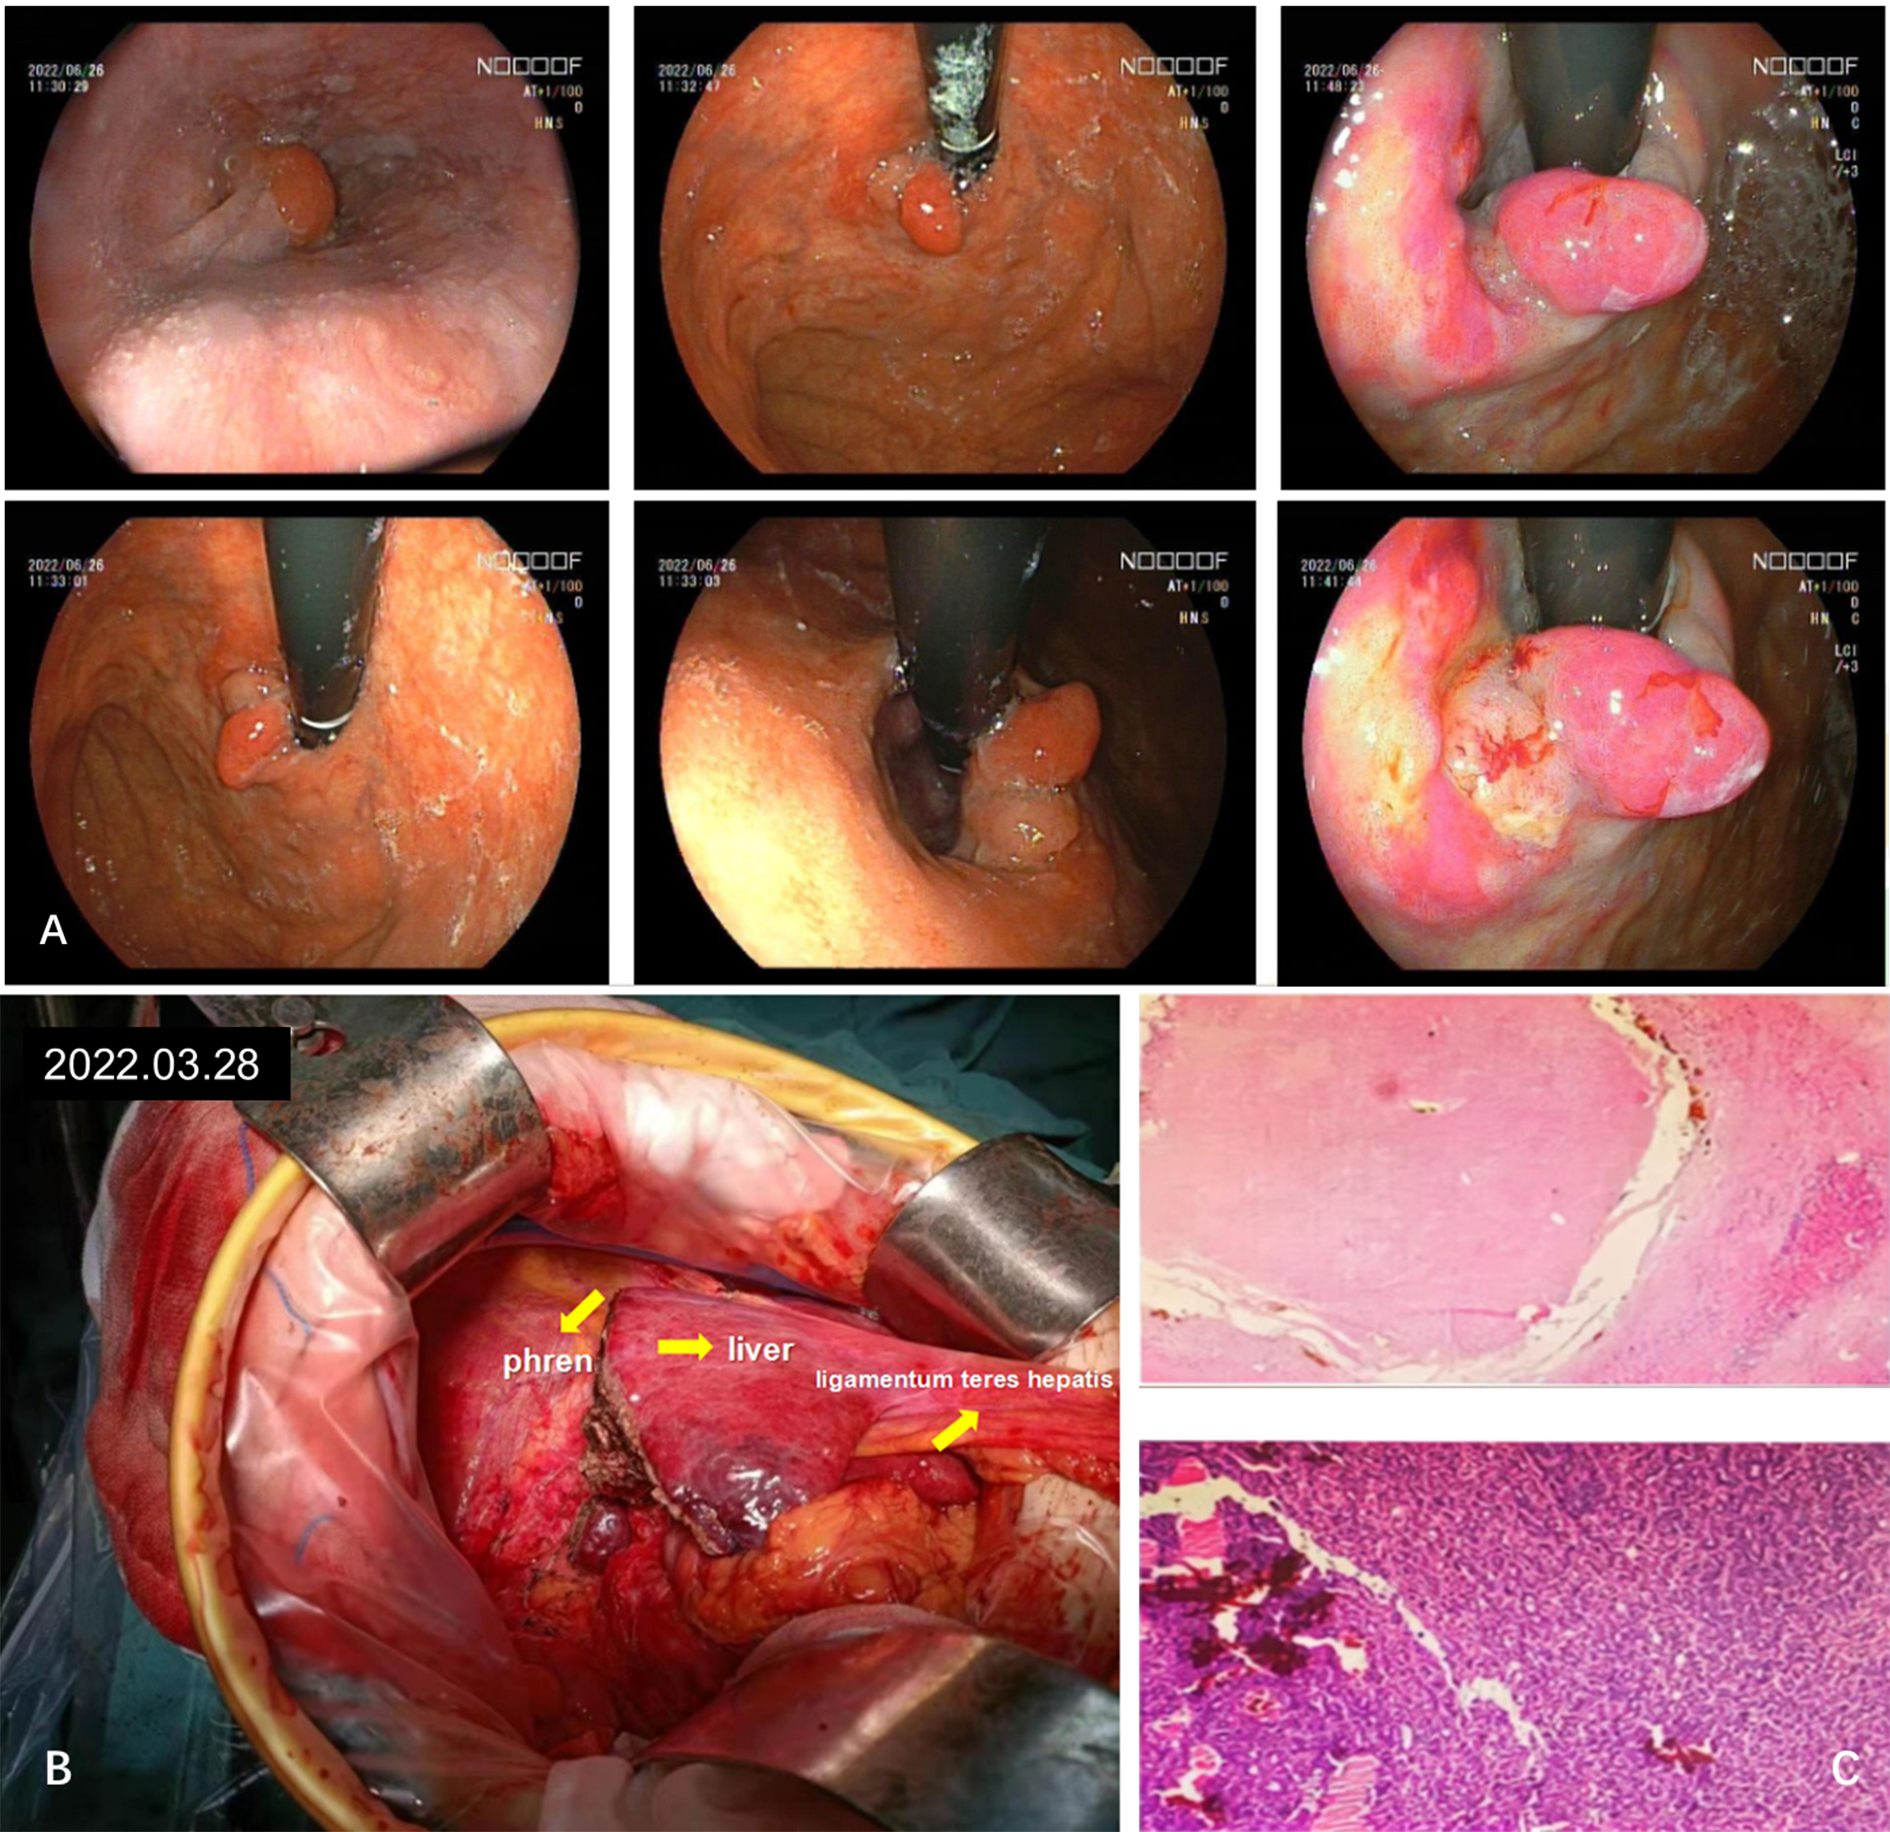

The patient was a 76-year-old male who presented to Lanzhou University First Hospital on August 5, 2021, with upper abdominal bloating and mild pain persisting for over one month. He reported no other symptoms, and an abdominal ultrasound conducted at another local hospital indicated the presence of a liver mass. His medical history included chronic hepatitis B for over 30 years, hypertension, diabetes, and cataract surgery with intraocular lens implantation. Upon physical examination, the patient exhibited normal skin and mucosal color without jaundice, a flat abdomen devoid of abdominal wall varices, and no remarkable gastrointestinal contour or peristalsis. There was no tenderness upon abdominal palpation, and the liver was palpable below the rib margin. Murphy’s sign was negative, and bowel sounds were noted at a rate of four times per minute. Laboratory tests revealed the following values within normal limits: white blood cell count (WBC: 5.03 × 10^9/L), neutrophil ratio (NEUT%: 68.8%), hemoglobin (HGB: 124 g/L), and platelet count (PLT: 205 × 10^9/L). Tumor markers were elevated, including alpha-fetoprotein (AFP: 289 U/mL), carbohydrate antigen 19-9 (CA 19-9: 109 U/mL), carcinoembryonic antigen (CEA: 1.4 ng/mL), and ferritin (519 ng/mL). Biochemical analysis indicated that aspartate aminotransferase (AST: 67 U/L), alanine aminotransferase (ALT: 216 U/L), total bilirubin (TBIL: 16.4 µmol/L), direct bilirubin (DBIL: 4.8 µmol/L), alkaline phosphatase (ALP: 216 U/L), gamma-glutamyl transferase (GGT: 371 U/L), and glucose (GLU: 6.59 mmol/L) were outside normal ranges. Tests for hepatitis B (2+, 5+) and hepatitis B virus DNA (HBV DNA < 100 IU/mL) were negative. Brain natriuretic peptide (BNP: 143.4 pg/mL) was outside the normal range. The enhanced abdominal CT scan revealed a large mass-like abnormal enhancement in the right lobe of the liver, suggesting hepatocellular carcinoma (HCC) with portal vein thrombosis in the main trunk as well as the left and right branches, cirrhosis, and portal hypertension (including esophageal and gastric fundus varices). Magnetic resonance imaging (MRI) of the liver revealed a large abnormally enhanced mass in the right lobe, suggesting hepatocellular carcinoma (HCC) with intratumoral hemorrhage and portal vein thrombosis in the main trunk as well as the left and right branches; cirrhosis, splenomegaly, a small amount of ascites, liver disease, and gallbladder disease (Figure 1). The patient was diagnosed with HCC of the right lobe, post-hepatitis B cirrhosis, grade 3 hypertension (very high risk), and type 2 diabetes, classified as stage IIIa according to the CNLC staging system (Figure 2). An initial multidisciplinary team (MDT) discussion resulted in a treatment plan that included hepatic artery infusion chemotherapy (HAIC) treatment (FOLFOX), combined with 200 mg sintilimab and sorafenib 0.4 g bid targeted therapy. The patient was discharged on August 16th, 2021. After discharge, oral sorafenib 0.4g bid targeted therapy was prescribed. On the second admission, a second MDT discussion was held to adjust the protocol: HAIC treatment and percutaneous liver puncture for radioactive 125I particle implantation, combined with 200 mg sintilimab and sorafenib targeted therapy. After the fifth admission, there was no significant change in the portal vein tumor thrombus. The third MDT was conducted, and on March 29, 2022, “percutaneous hepatic puncture radioactive 125I particle implantation” radiation therapy was performed. Additionally, because the patient could not tolerate bisphosphonates, the treatment was changed to once-daily targeted therapy with 8 mg of lenvatinib. The patient underwent abdominal CT (plain + enhanced) at the sixth admission on June 21, 2022, compared with the previous scan on March 28, 2022 showed a lesion in the right lobe of the liver with little change, along with occlusion of the main portal vein and portal spongiosis, which remained little changed from the previous scan (Figure 2). After comprehensive consideration of the timing of surgical resection following successful conversion, the decision was made to perform surgical treatment. Subsequently, another preoperative evaluation was conducted, which included gastroscopy, revealing a 0-Ia+IIc type lesion can be seen near the anterior wall of the cardia, with a size of about 3 × 2 cm and chronic atrophic gastritis (Figure 3A). After the fourth MDT, the gastric tumor was initially resected via laparoscopy combined with endoscopy under general anesthesia on July 4, 2022 (endoscopic mucosal resection, partial gastrectomy, and D1 lymph node dissection). Due to the patient’s poor cardiopulmonary function during the operation, the laparoscopic surgery was interrupted and converted into an open procedure for right hepatectomy and cholecystectomy (Figure 3B). The postoperative gastric histopathology report indicated ectopic hyperplasia of adenoepithelial hyperdifferentiated epithelial endothelium and focal carcinomatous lesions (Figure 3C). Two trans arterial chemoembolization (TACE) procedures were performed on September 13, 2022, and April 3, 2023, as adjuvant treatment following hepatic resection, in accordance with the Guidelines for the Diagnosis and Treatment of Primary Hepatocellular Carcinoma (2022 edition). Postoperative abdominal CT and MRI were performed on December 18, 2023, which revealed the disappearance of the portal vein thrombus and widening of the hepatic fissure (Figure 4). Remarkably, the patient demonstrated a favorable prognosis, recovering well and remaining free of tumor recurrence or metastasis during over eight months of follow-up.

Figure 3

Diagnosis and intraoperative imaging of hepatocellular carcinoma combined with early gastric cancer. (A) A gastroscopic lesion of type 0-Ia+IIc is observed near the anterior wall of the cardia. (B) Intraoperative image. (C) Extensive sampling of liver tissue revealed all necrotic tissue, while gastric tissue exhibited chronic inflammation and focal low-grade intraepithelial tumors, as observed by hematoxylin-eosin (HE) staining.